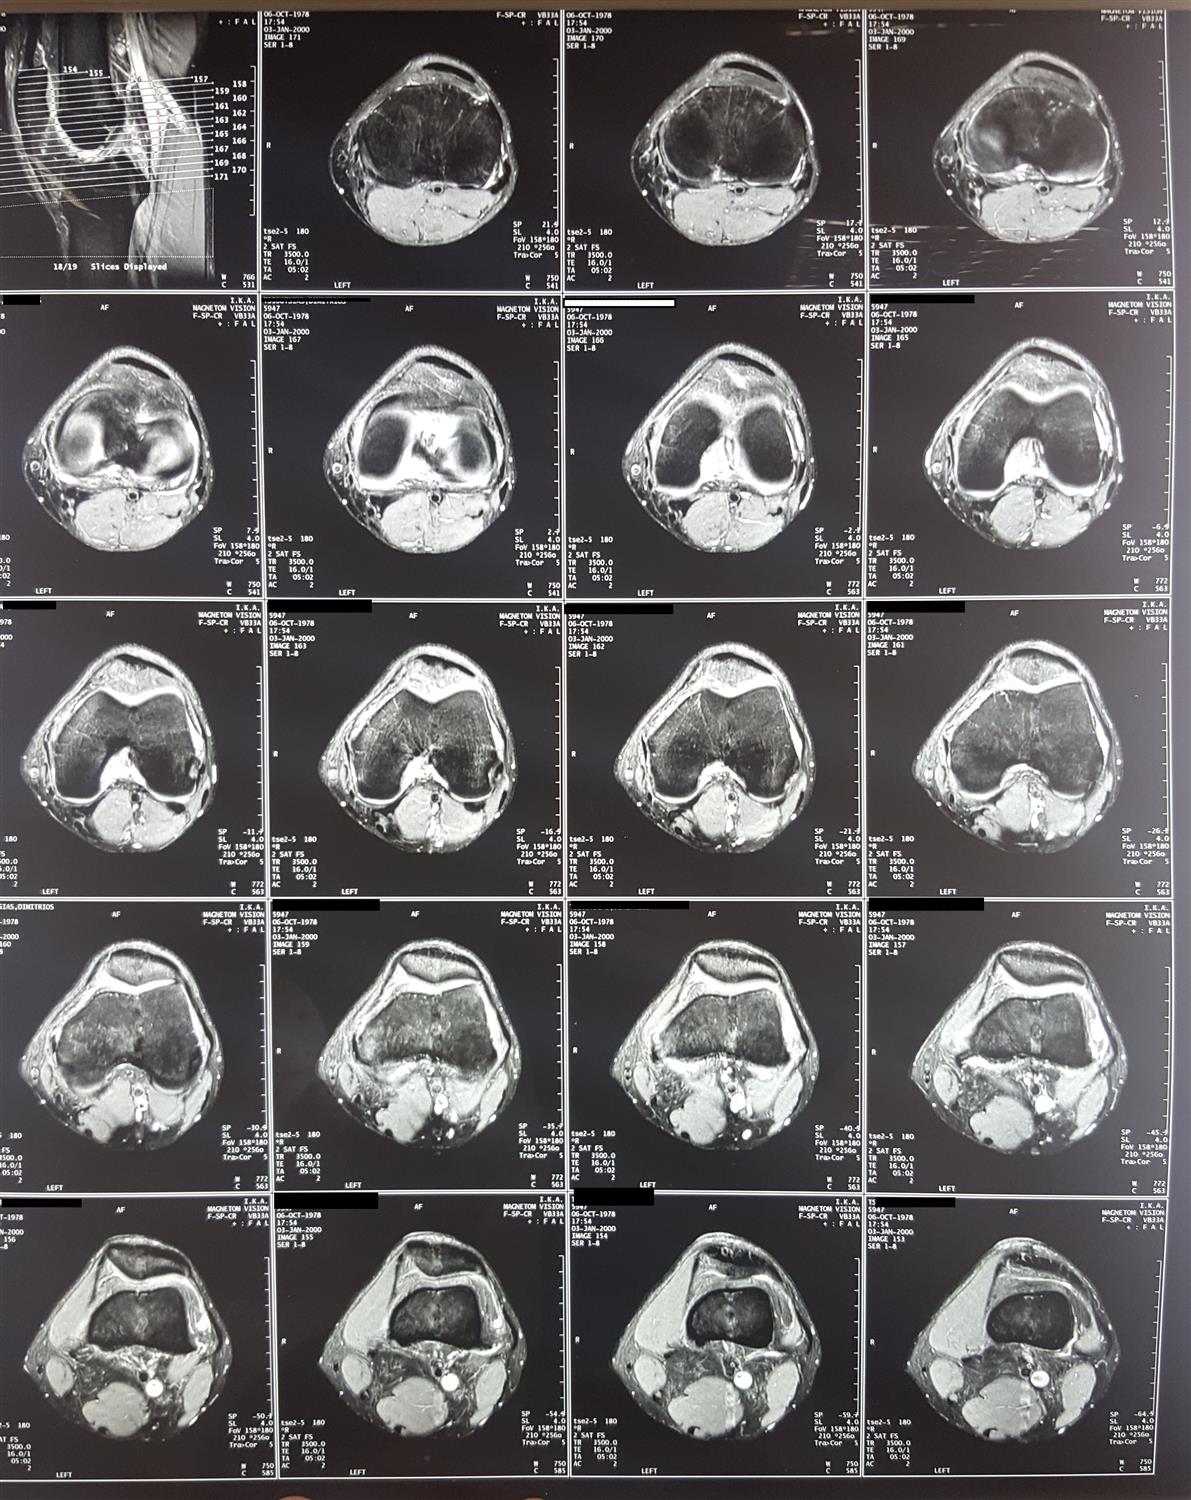

Introduction Spectrum of disease entities from single, focal defects to advanced degenerative disease of articular (hyaline) cartilage Epidemiology incidence 5-10% of people > 40 years old have high grade chondral lesions location chronic ACL tear anterior aspect of lateral femoral chondyle and posterolateral tibial plateau osteochondritis dissecans 70% of lesions found in posterolateral aspect of medial femoral condyle Pathophysiology mechanism of injury acute trauma or chronic repetitive overload impaction resulting in cartilage softening; fissuring; flap tears; or delamination the cause of OCD is unknown pathomechanics impaction forces greater than 24 MPa will disrupt normal cartilage cellular biology cartilage injuries have limited spontaneous healing and propensity to worsen over time Anatomy See Articular Cartilage Basic Science Classification Outerbridge Arthroscopic Grading System Grade 0 Normal cartilage Grade I Softening and swelling Grade II Superficial fissures Grade III Deep fissures, without exposed bone Grade IV Exposed subchondral bone ICRS (International Cartilage Repair Society) Grading System Grade 0 Normal cartilage Grade 1 Nearly normal (superficial lesions) Grade 2 Abnormal (lesions extend < 50% of cartilage depth) Grade 3 Severely abnormal (>50% of cartilage depth) Grade 4 Severely abnormal (through the subchondral bone) Presentation History commonly present with history of precipitating trauma some defects found incidentally on MRI or arthroscopy Symptoms asymptomatic vs. localized knee pain may complain of effusion, motion deficits, mechanical symptoms (e.g., catching, instability) Physical exam inspection look for background factors that predispose to the formation of articular defects joint laxity malalignment compartment overload motion assess range of motion, ligamentous stability, gait Imaging Radiographs indications used to rule out arthritis, bony defects, and check alignment recommended views standing AP, lateral, merchant views optional views semiflexed 45 deg PA views most sensitive for early joint space narrowing long-leg alignment views determine the mechanical axis CT scan indications better evaluation of bone loss findings used to measure TT-TG when evaluating the patello-femoral joint MRI indication most sensitive for evaluating focal defects views Fat-suppressed T2, proton density, T2 fast spin-echo (FSE) offer improved sensitivity and specificity over standard sequences dGEMRIC (delayed gadolinium-enhanced MRI for cartilage) and T2-mapping are evolving techniques to evaluate cartilage defects and repair Studies Laboratory may be used to rule out inflammatory disease Treatment Nonoperative rest, NSAIDs, physiotherapy, weight loss indications first line of treatment when symptoms are mild viscosupplementatoin, corticosteroid injections, unloader brace indications controversial may provide symptomatic relief but healing of defect is unlikely Operative debridement/chondroplasty vs. reconstruction techniques indications failure of nonoperative management acute osteochondral fractures resulting in full-thickness loss of cartilage technique treatment is individualized, there is no one best technique for all defects decision-making algorithm is based on several factors patient factors age skeletal maturity low vs. high demand activities ability to tolerate extended rehabilitation defect factors size of defect location contained vs. uncontained presence or absence of subchondral bone involvement basic algorithm (may vary depending on published data) femoral condyle defect correct malaligment, ligament instability, meniscal deficiency measure size < 4 cm2 = microfracture or osteochondral autograft transfer (pallative if older/low demand) > 4 cm2 = osteochondral allograft transplantation or autologous chondrocyte implantation patellofemoral defect address patellofemoral maltracking and malalignment measure size < 4 cm2 = microfracture or osteochondral autograft transfer > 4 cm2 = autologous chondrocyte implantation (microfracture if older/low demand) Surgical Techniques Debridement / Chondroplasty overview goal is to debride loose flaps of cartilage removal of loose chondral fragments may relieve mechanical symptoms short-term benefit in 50-70% of patients benefits include simple arthroscopic procedure, faster rehabilitation limitations problem is exposed subchondral bone or layers of injured cartilage unknown natural history of progression after treatment Fixation of Unstable Fragments overview need osteochondral fragment with adequate subchondral bone technique debride underlying nonviable tissue consider drilling subchondral bone or adding local bone graft fix with absorbable or nonabsorbable screws or devices benefits best results for unstable osteochondritis dissecans (OCD) fragments in patients with open physis limitations lower healing rates in skeletally mature patients nonabsorbable fixation (headless screws) should be removed at 3-6 months Marrow Stimulation Techniques overview goal is to allow access of marrow elements into defect to stimulate the formation of reparative tissue includes microfracture, abrasion chondroplasty, osteochondral drilling microfracture technique defect is prepared with stable vertical walls and the calcified cartilage layer is removed awls are used to make multiple perforations through the subchondral bone 3 - 4 mm apart protected weight bearing and continuous passive motion (CPM) are used while mesenchymal stem cells mature into mainly fibrocartilage benefits include cost-effectiveness, single-stage, arthroscopic best results for acute, contained cartilage lesions less than 2 cm x 2cm limitations poor results for larger defects >2 cm x 2cm does not address bone defects requires limitation of weight bearing for 6 - 8 weeks Osteochondral autograft / Mosaicplasty overview goal is to replace a cartilage defect in a high weight bearing area with normal autologous cartilage and bone plug(s) from a lower weight bearing area chondrocytes remain viable, bone graft is incorporated into subchondral bone and overlying cartilage layer heals. technique a recipient socket is drilled at the site of the defect a single or multiple small cylinders of normal articular cartilage with underlying bone are cored out from lesser weight bearing areas (periphery of trochlea or notch) plugs are then press-fit into the defect limitations size constraints and donor site morbidity limit usage of this technique matching the size and radius of curvature of cartilage defect is difficult fixation strength of graft initially decreases with initial healing response weight bearing should be delayed 3 months benefits include autologous tissue, cost-effectiveness, single-stage, may be performed arthroscopically Osteochondral allograft transplantation overview goal is to replace cartilage defect with live chondrocytes in mature matrix along with underlying bone fresh, refrigerated grafts are used which retain chondrocyte viability may be performed as a bulk graft (fixed with screws) or shell (dowels) grafts technique match the size and radius of curvature of articular cartilage with donor tissue a recipient socket is drilled at the site of the defect an osteochondral dowel of the appropriate size is cored out of the donor the dowel is press-fit into place benefits include ability to address larger defects, can correct significant bone loss, useful in revision of other techniques limitations limited availability and high cost of donor tissue live allograft tissue carries potential risk of infection Autologous chondrocyte implantation (ACI) overview cell therapy with goal of forming autologous "hyaline-like" cartilage technique arthroscopic harvest of cartilage from a lesser weight bearing area in the lab, chondrocytes are released from matrix and are expanded in culture defect is prepared, and chondrocytes are then injected under a periosteal patch sewn over the defect during a second surgery benefits may provide better histologic tissue than marrow stimulation long term results comparable to microfracture in most series include regeneration of autologous tissue, can address larger defects limitations must have full-thickness cartilage margins around the defect open surgery 2-stage procedure prolonged protection necessary to allow for maturation Patellar cartilage unloading procedures Maquet (tibia tubercle anteriorization) indicated only for distal pole lesions only elevate 1 cm or else risk of skin necrosis contraindications superior patellar arthrosis (scope before you perform the surgery) Fulkerson alignment surgery (tibia tubercle anteriorization and medialization indications (controversial) lateral and distal pole lesions increased Q angle contraindications superior medial patellar arthrosis (scope before you perform the surgery) skeletal immaturity Matrix-associated autologous chondrocyte implantation overview example is "MACI" cells are cultured and embedded in a matrix or scaffold matrix is secured with fibrin glue or sutures benefits only FDA approved cell therapy for cartilage in the USA include ability to perform without suturing, may be performed arthroscopically limitations 2-stage procedure Expense

LEFT TIBIA OSTEOCHONDRAL AND METAPHYSEAL LESIONS IN A 39M (C101043) Knee & Sports - Articular Cartilage Defects of Knee HPI - 2 w ago patient felt intense (10/10) left knee pain while playing football without any obvious injury. Localized tender edema developed on his left upper tibila metaphysis on the medial side. After a short oral NSAID regimen and ice application his pain subsided almost completely (2/10). He underwent CT and MRI (+IV paramagnetic agent) examination What is your opinion on cruciate ligaments integrity based on 02-21-2018 MRI sequences? 2/24/2018 196 8 6 Cartilage lesion with mild valgus mechanical alignment (C1827) Knee & Sports - Articular Cartilage Defects of Knee HPI - 36 year old active male with lateral knee pain. Previous hx of acl recon. Did well with that. Recently started to have lateral knee pain. Initial arthroscopy did reveal Grade 3-4 lateral joint chondromalacia. Well contained lesions. This was debrided and microfractured. ACL graft was intact. Continued to have pain. all pain is lateral knee. Now my Plan is for ACI vs DeNovo. Full length scanogram films shows mechanical axis falls through the lateral joint. Not terrible but not normal either. Any indication for distal femoral osteotomy along with cartilage restoration? Stage or do at same time? Plan of care? 3/17/2014 60 2 4 Patellar chondropathy (C1731) Knee & Sports - Articular Cartilage Defects of Knee HPI - Painless knee crepitus What is the MRI finding? 12/30/2013 350 0 5 See More See Less